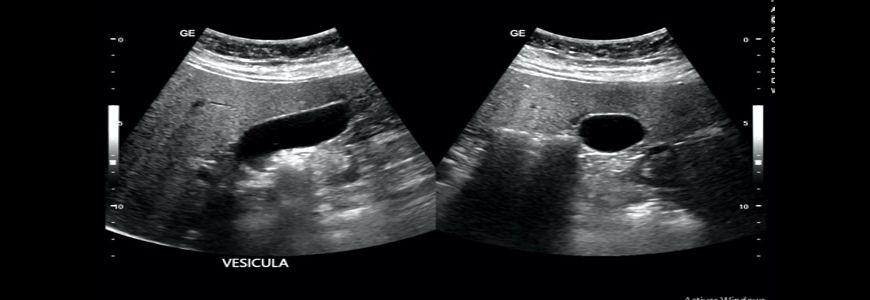

Ecografia Abdominal

Utiliza una pequeña sonda llamada transductor y se coloca gel directamente sobre la piel. Las ondas sonoras de alta frecuencia viajan desde la sonda a través del gel y hacia adendro del cuerpo. La sonda recoge los sonidos que rebotan y un computador utiliza esas ondas sonoras para crear posteriormente una imagen